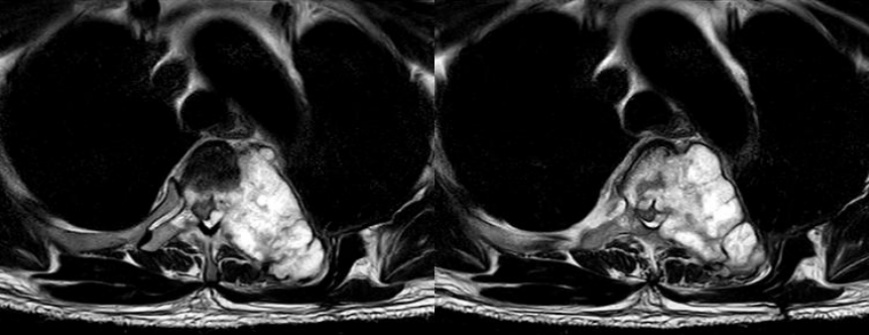

2025年2月,许先生前往台湾接受了左侧第四肋骨部分切除术,术后病理提示为软骨肉瘤。本以为这场与肿瘤的对抗已初见成效,没想术后仅半年,PET/CT 复查显示,他的左侧第四肋骨残端近胸椎侧出现了疑似肿瘤残留病灶,且已部分侵犯胸椎。同年12月,再次复查局部磁共振提示他的胸椎T4节段出现肿瘤转移,巨大的软组织肿块向椎管内延伸,严重压迫脊髓,还累及了多个椎体、肋骨与神经根,并且出现了脊髓压迫的症状——双下肢肌力开始下降,活动逐渐受限。短短两周内,他突然出现双下肢麻木伴无力的症状,紧急在新加坡当地的医院接受姑息性减压手术,可这场手术并未带来转机,反而让他的双下肢肌力降至M0级彻底瘫痪。

术前MR影像图